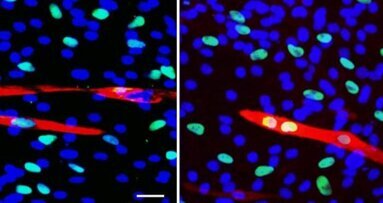

L’équipe de Gordana Vunjak-Novakovic (de l’université Columbia, New York) a réussi à ensemencer un os de veau, débarrassé de ses cellules, avec des cellules souches adultes humaines de la moelle osseuse.

Préalablement découpé aux dimensions voulues, cet os a été placé dans un bioréacteur fait, lui aussi, sur mesure. Le bioréacteur a apporté en profondeur les nutriments nécessaires à la prolifération et à la différenciation des cellules osseuses. Au bout de cinq semaines, un os vivant avait remplacé la structure inerte initiale. Guy Daculsi de l’Inserm considère que le processus est maintenant au point : « Des sociétés se positionnent déjà à l’étranger pour reproduire des structures osseuses plus complexes en bioréacteur. En Europe, le projet “Reborne”, coordonné par l’Inserm, a lancé cinq essais cliniques de reconstitution osseuse chez l’homme, pour les chirurgies orthopédique et maxillo-faciale ».